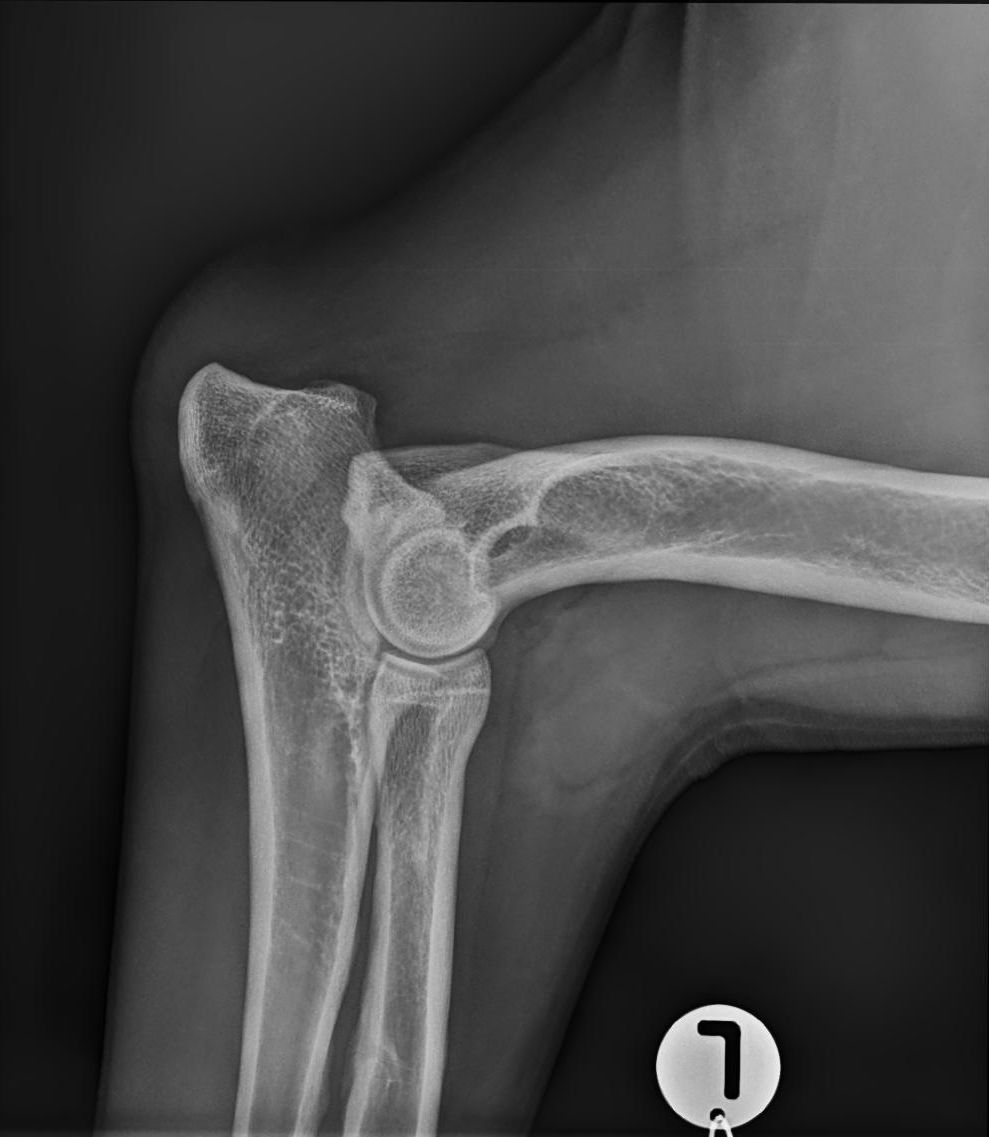

ED –Röntgenuntersuchung des Ellbogens

ED ist die Kurzform für Ellbogendysplasie. Es handelt sich hierbei um eine vererbte Entwicklungsstörung des Ellbogengelenks großer Rassen. Wiederum können Körpermasse und Fütterungsfehler die Krankheit begünstigen.

Die ED beginnt in der späten Wachstumsphase bei vier bis acht Monate alten Jungtieren. Dabei kommt es zu schmerzhaften Veränderungen am Gelenk, die die Bewegungsfreiheit einschränken und zu Lahmheit führen. Die Krankheit schreitet lebenslang fort und ist nicht heilbar, eine weitgehende Schmerzfreiheit kann aber in vielen Fällen erreicht werden.

ED Grad 0

ED Grad  3